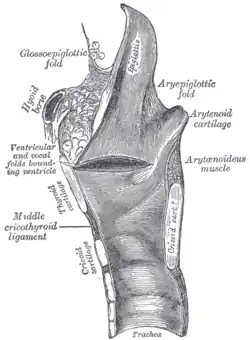

Vue bouche ouverte pour l'évaluation du grade de Malampati.

Vue bouche ouverte pour l'évaluation du grade de Malampati. Coupe sagittale du larynx et de la trachée